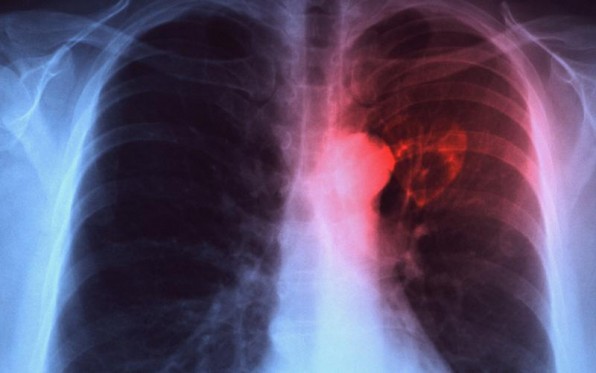

Επανεμφάνιση φυματίωσης στην Ελλάδα λόγω πτώσης βιωτικού επιπέδου

Για επανεμφάνιση της φυματίωσης λόγω πτώσης του βιωτικού επιπέδου στην Ελλάδα κάνουν λόγο οι επιστήμονες. Μάλιστα, ενώ τα προηγούμενα χρόνια τα περισσότερα περιστατικά φυματίωσης παρατηρούνταν σε αλλοδαπούς, τώρα πια τα ποσοστά είναι τα ίδια και στους Έλληνες. Κι ενώ στη χώρα μας υπάρχει πολύ καλό σύστημα επιτήρησης της φυματίωσης, δυστυχώς η νόσος υποδηλώνεται.